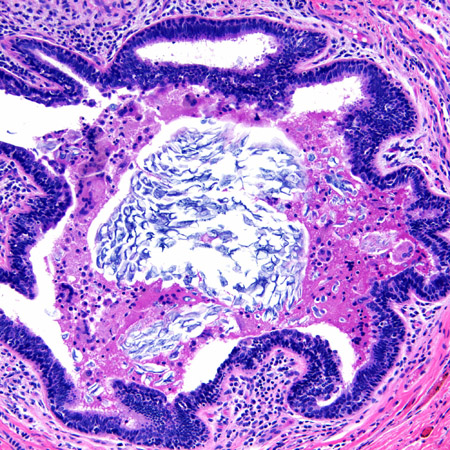

In lactational mastitis, milk stasis or milk overproduction, coupled with infection from bacteria entering the breast via a traumatised nipple (e.g., cracked or fissured) and/or from the infant's mouth, can lead to mastitis.[1] Transient breast enlargement from maternal hormones in neonates makes them vulnerable to mastitis.[Figure caption and citation for the preceding image starts]: Lactational mastitis: microscopy image showing hyper-secretory glands associated with inflammationFrom the collection of Liron Pantanowitz, MD, Tufts University School of Medicine, MA [Citation ends].